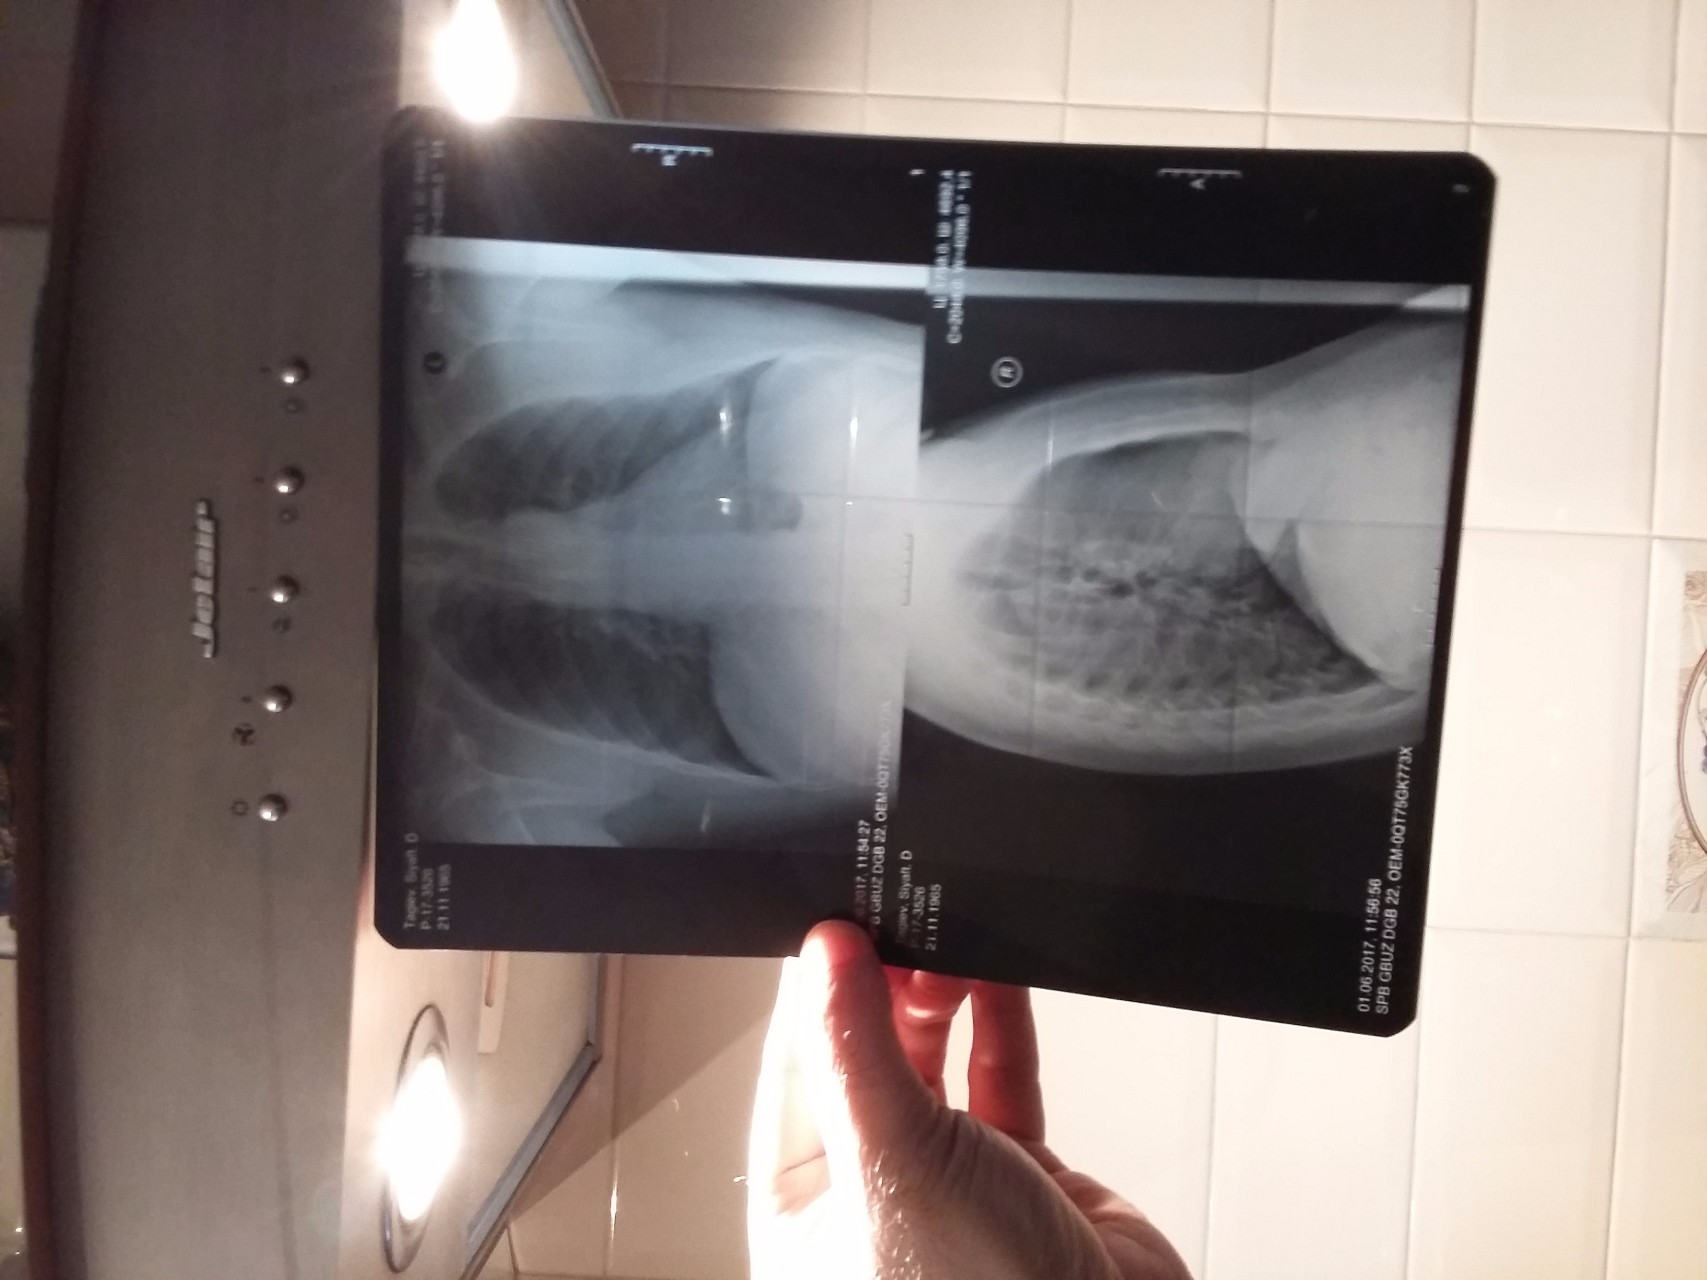

Рентгеновские технологии: усиленные экраны 35x35